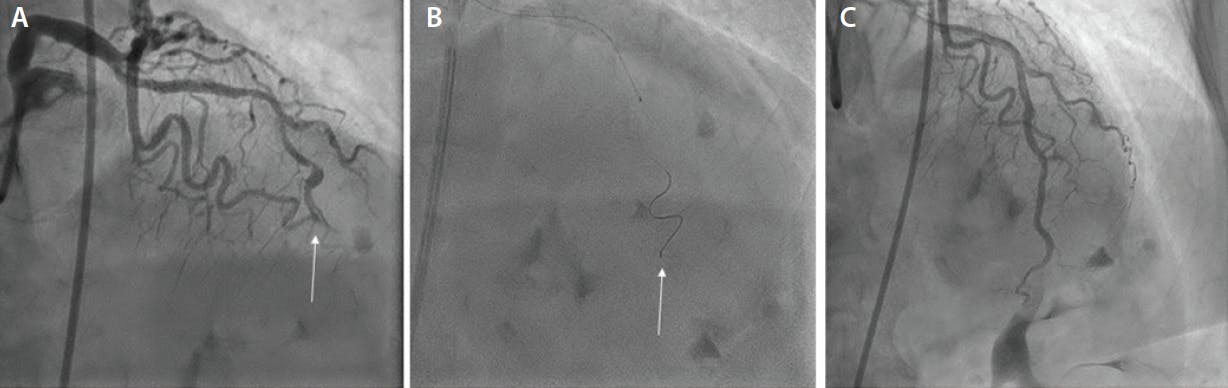

Guidewire selection is a critical key step for successful percutaneous management of IOCDs. In such situations, the ideal wire should have a soft tip, high torque control, excellent flexibility, and good trackability. It has been reported in a large series of consecutive IOCDs that the Suoh 03 guidewire (Asahi Intecc USA, Inc.) has a higher chance of navigating through the dissected segment following the true lumen, with a lower risk of advancement into the periadventitial space (Figure 1).6 The highly flexible tip of the Suoh 03 guidewire allows the operator to immediately recognize the progression of the wire into the subintimal space with an evident tip deflection, in a sort of “guidewire curling”; straight tip progression is strongly indicative of intraluminal tracking. Conversely, if true lumen wiring with the soft wires fails, CTO guidewires (with intermediate or high tip load) can be used to re-enter the distal true lumen. These wires can be advanced over a dual-lumen microcatheter to facilitate their delivery and enhance wire manipulation.

Figure 1. Wiring: long and occlusive spiral dissection of a very tortuous mid left anterior descending (white arrow) (A); successful Suoh 03 guidewire advancement supported by a microcatheter (white arrow) (B); and final result after multiple DES implantations (C).